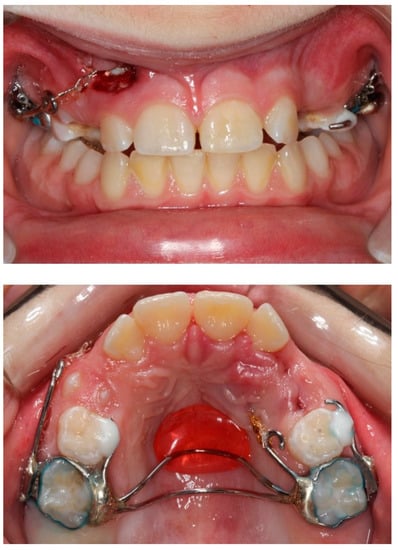

Extra-oral examination of the child revealed a convex profile, slightly reduced lower facial height and increased labionasal angle. Intra-oral clinical examination showed a mixed dentition in Class II molar relationship, reduced overjet (2 mm) and overbite (10%) (Figure 1). Patient’s oral hygiene was good.

Figure 1. Pre-treatment extra- and intra-oral photographs.